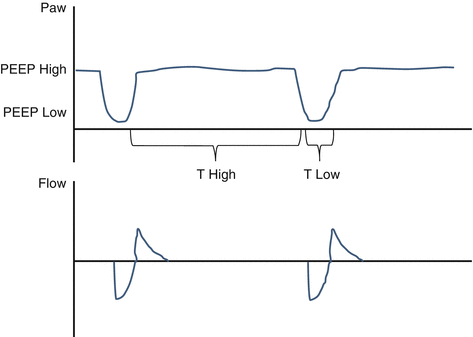

Airway pressure release ventilation (APRV) is a combination of pressure-controlled ventilation and inverted ratio ventilation on a time-triggered, pressure-targeted, and time-cycled mode (Fig. 47.3). A higher and a lower PEEP are set, and 80–95% of the respiratory cycle is spent during inspiration at the higher PEEP. The patient is allowed to breathe spontaneously during both high and low PEEP. The mean airway pressure increases without much increase in the peak pressure, favoring lung protection. This mode has been found to be associated with shorter ICU stay and duration of ventilation in patients with ARDS, but contradictory literature still exists, mostly in regard to the lack of evidence of mortality benefit.

Fig. 47.3 Airway pressure release ventilation (APRV)